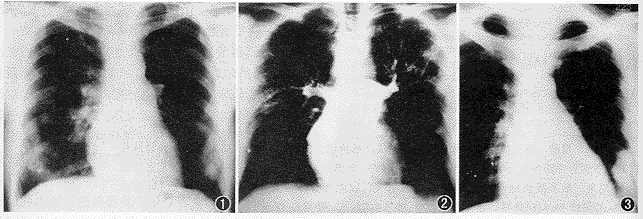

20例可疑单纯肺栓塞与肺栓塞合并肺梗死病人的影像学表现:两肺透亮度增高11例(图1),肺动脉扩张4例,血流减弱或消失(根据胸部平片和肺动脉造影综合分析)12例(图2),心脏形态大小改变2例,肺内实变阴影6例(图3),肺内索条状影2例(图1),单侧少量胸腔积液2例,病侧横膈升高3例,核素肺灌注异常11例(图4),肺动脉管腔充盈缺损7例,肺动脉阻塞或狭窄6例(图5)。

图1 两肺透亮度增强,两下肺见少许索条状阴影,右下尤著 图2 选择性肺动脉造影,仅两上肺部分肺动脉显影 图3 左下肺大片状密度增高影